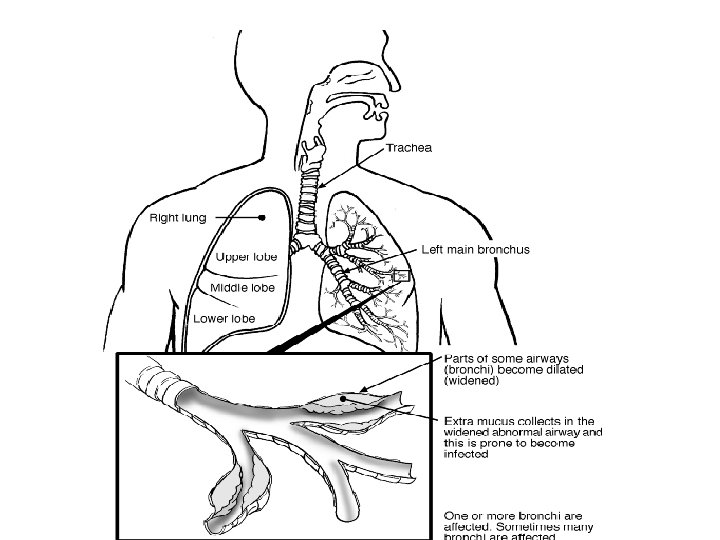

BRONCHIECTASIS • • • Definition: Abnormal and permanent dilation of bronchi. Focal or diffuse distribution It is a disorder that typically affects older individuals approximately 2/3 of patients are women It is usually acquired but may result from an underlying genetic or congenital defect of airway defences Clinical consequences – • chronic and recurrent infection and • Pooling of secretions in dilated airways.

Clinical features of bronchiectasis Due to accumulation of pus in dilated bronchi • Chronic productive cough usually worse in mornings and often brought on by changes of posture. • Sputum often copious and persistently purulent in advanced disease. • Halitosis is a common accompanying feature • SOB

Investigations • Bacteriological and mycological examination of sputum • In addition to common respiratory pathogens, sputum culture may reveal Pseudomonas aeruginosa, fungi such as Aspergillus and various Mycobacteria. • Frequent cultures are necessary to ensure appropriate treatment of resistant organisms. • Radiological examination Bronchiectasis, unless very gross, is not usually apparent on a chest X-ray. • In advanced disease, thickened airway walls, cystic bronchiectatic spaces, and associated areas of pneumonic consolidation or collapse may be visible. • CT scan of chest is much more sensitive, and shows thickened dilated airways